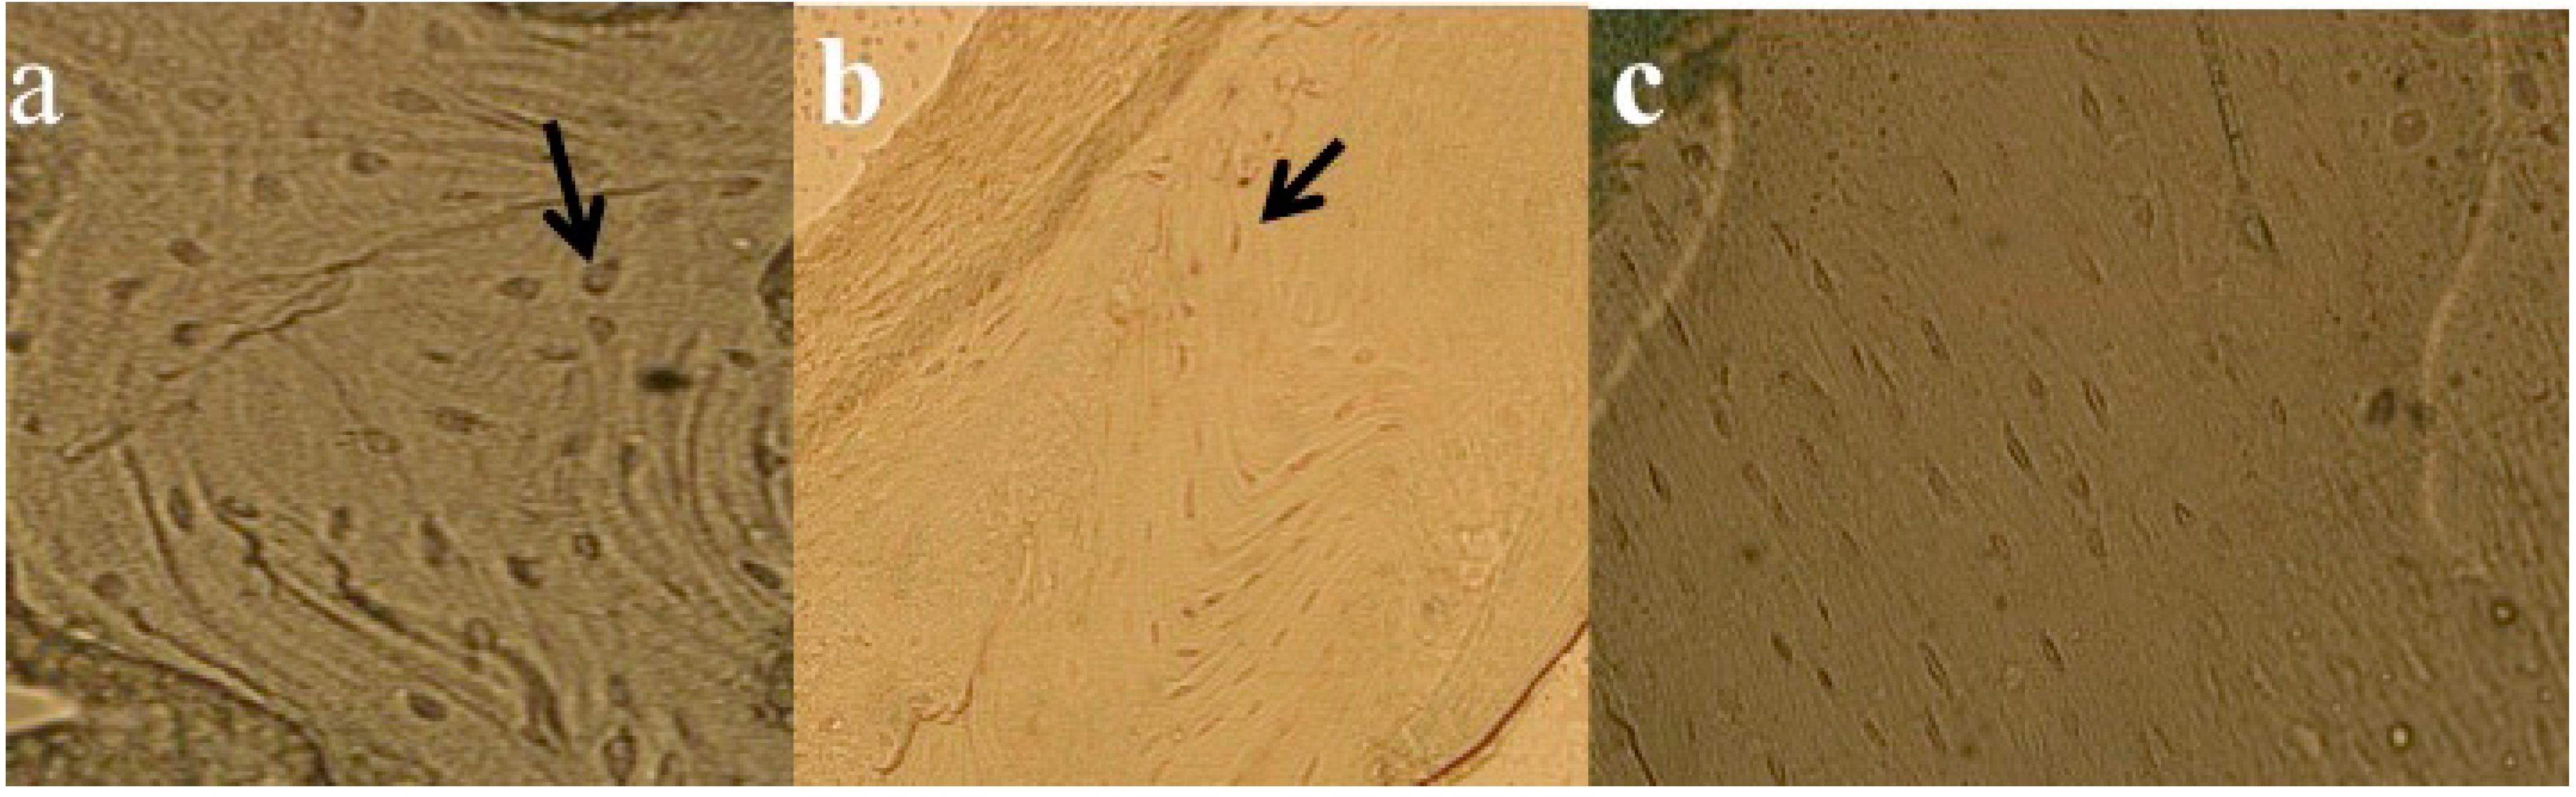

3.3. Transmission Electron Microscopy Results